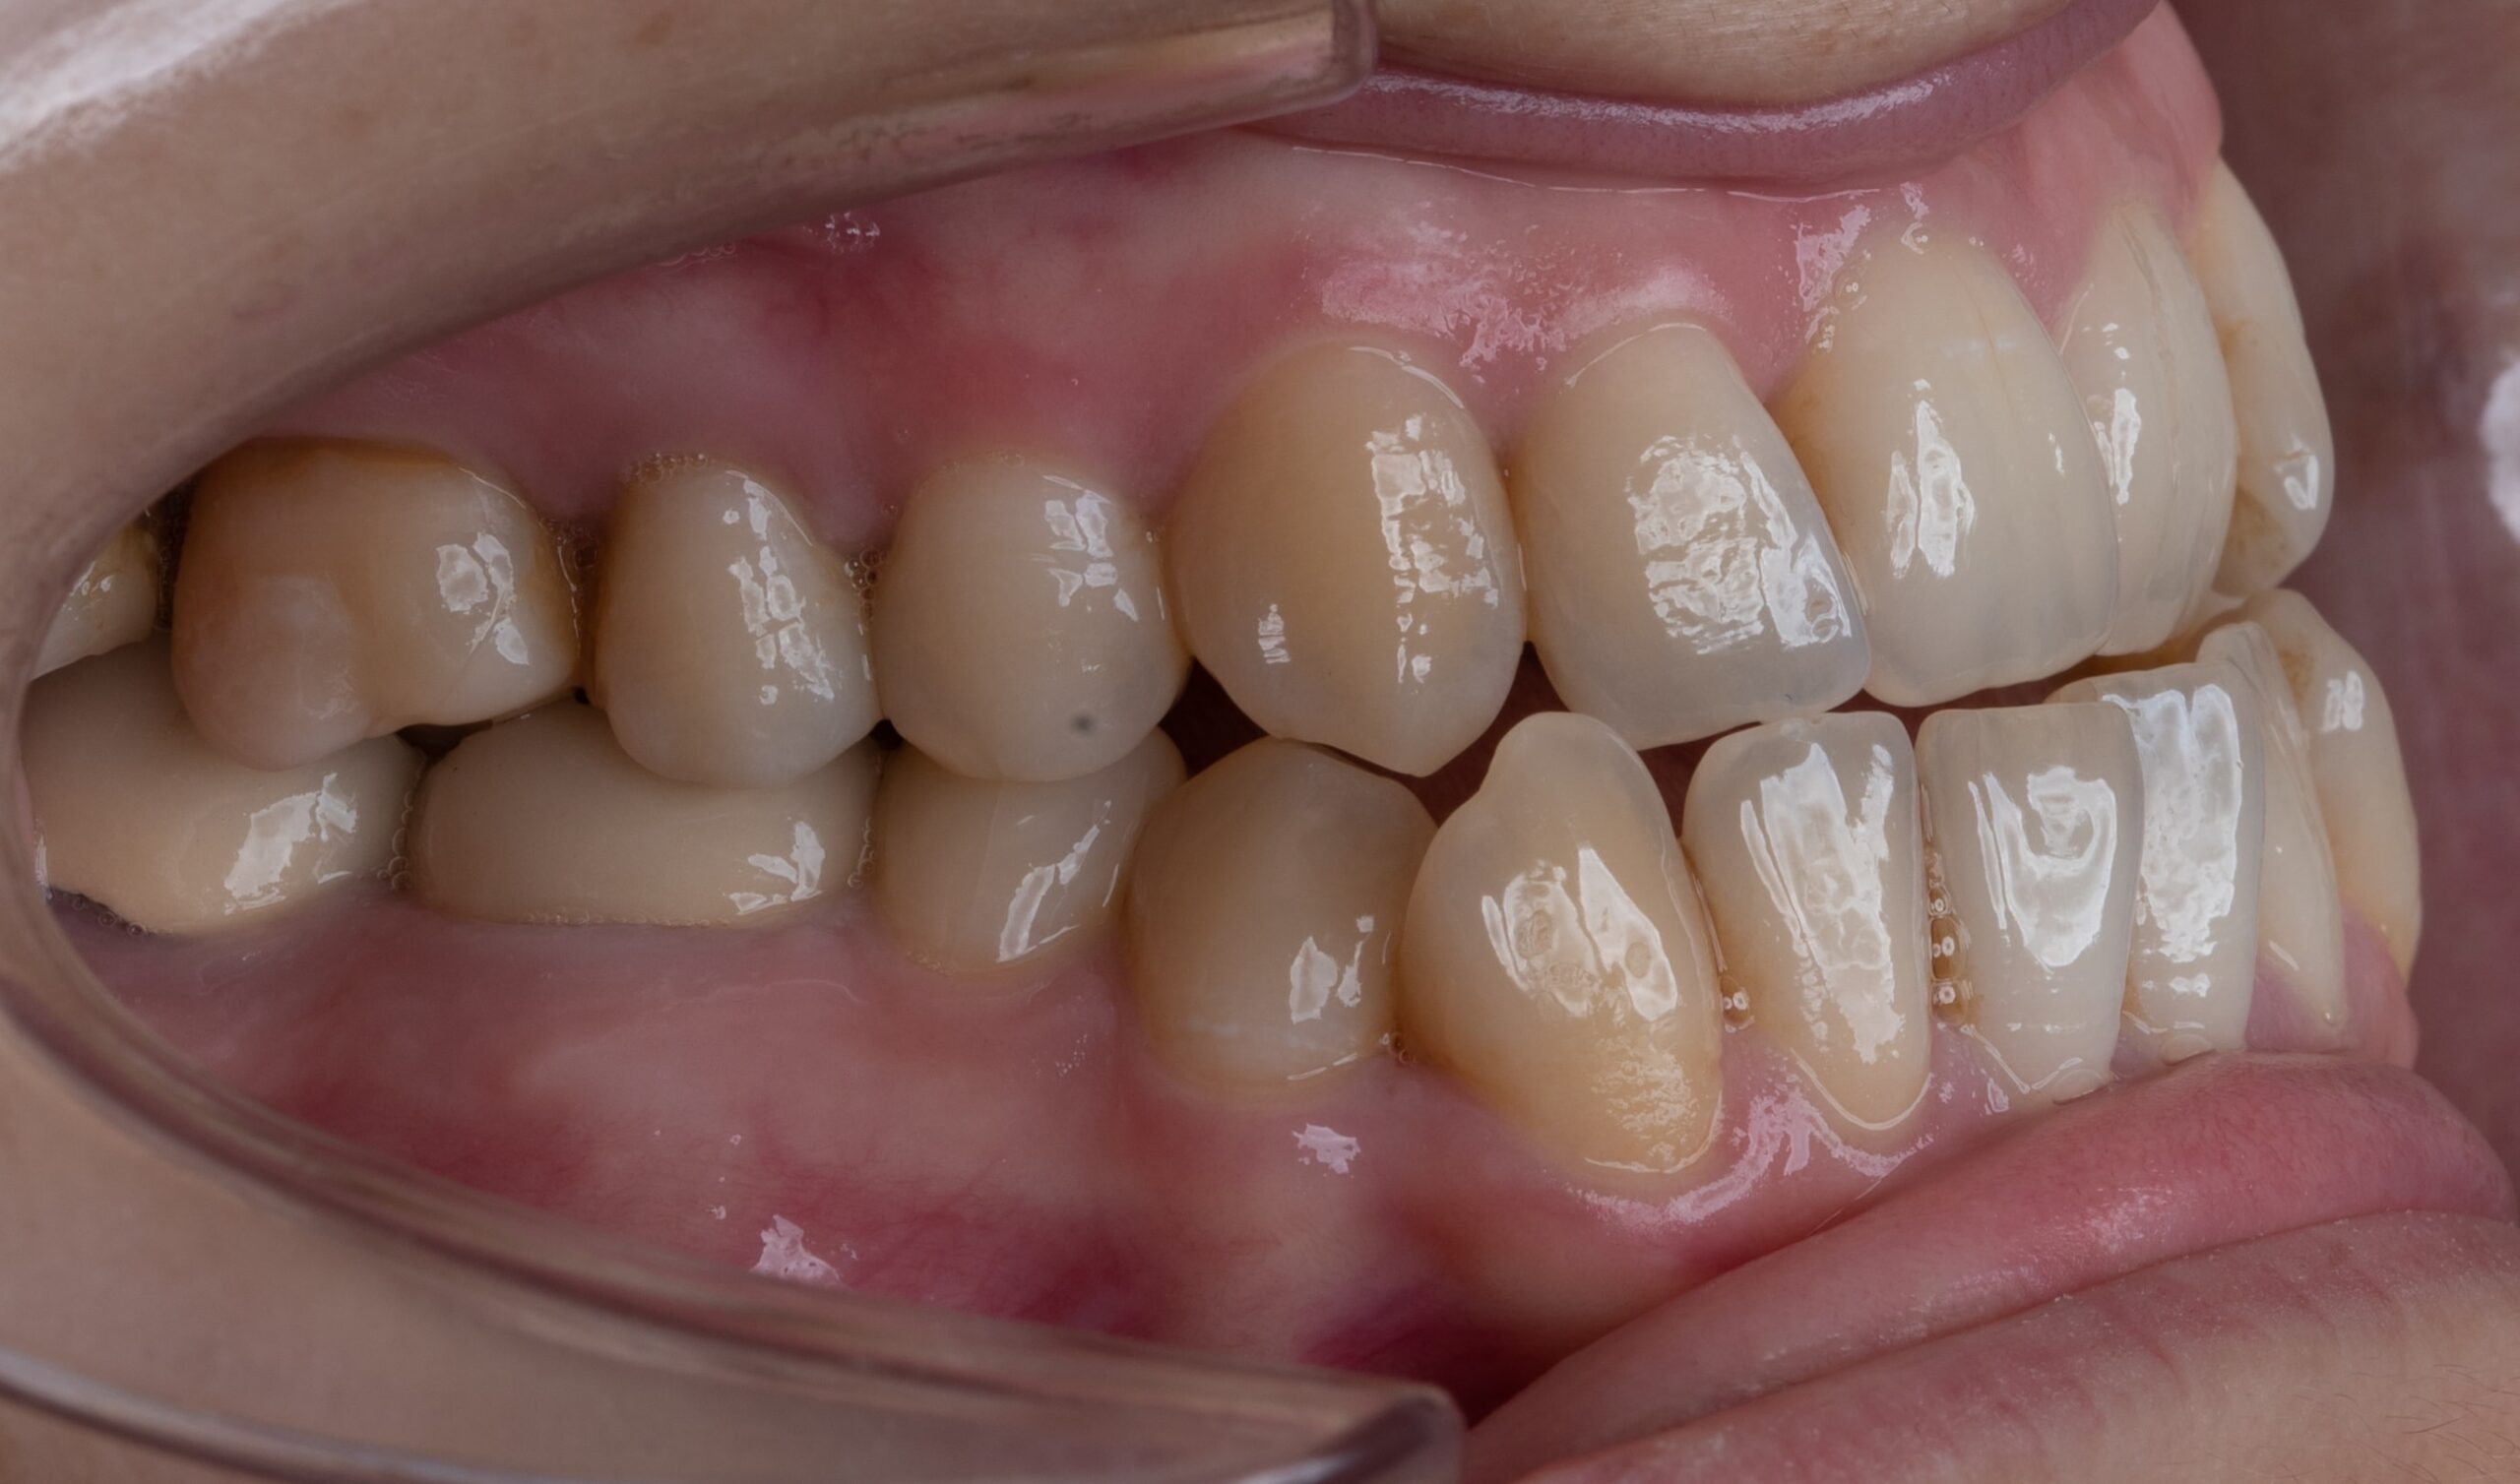

Burada yüz profilinin, gülümsemenin ve kapanışın nasıl değiştiğini gösteren bazı ortognatik cerrahi vaka örnekleri yer almaktadır. Öncesi ve sonrası fotoğrafları, ameliyatla elde edilen çene pozisyonunu, yüz simetrisi ve genel estetikteki dramatik iyileşmeleri açıkça göstermektedir. Bu görüntüler ortognatik cerrahinin hem görünüm hem de işlev üzerinde yaratabileceği olumlu etkiyi vurgulamaktadır.